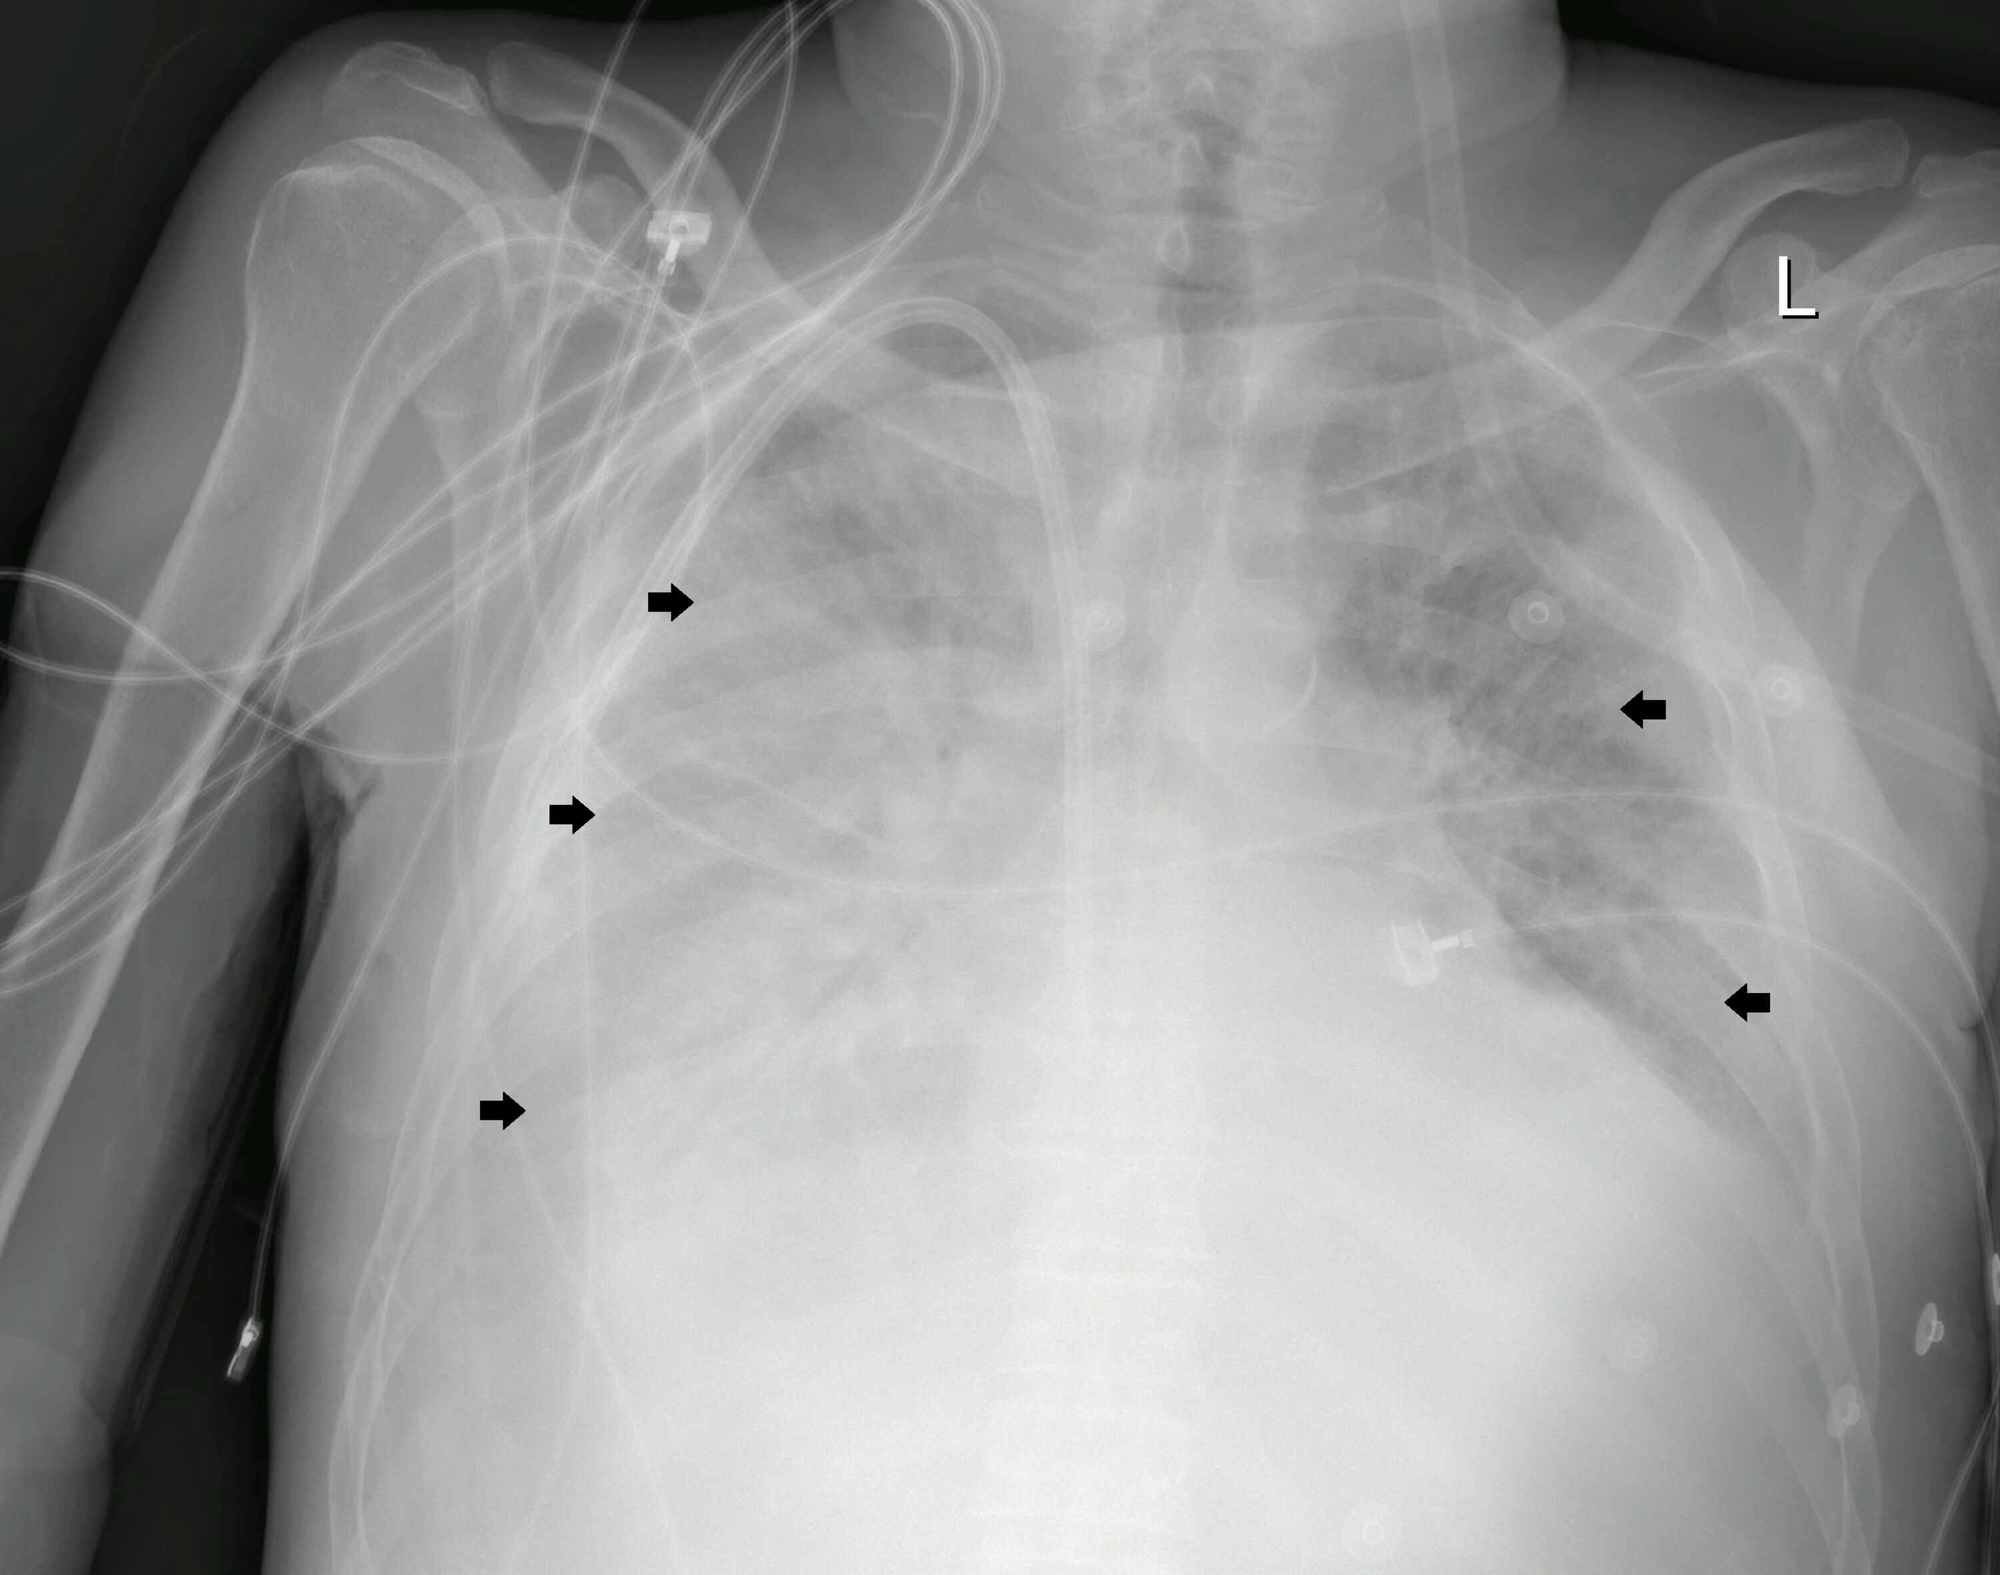

After 14 days in the high dependency unit, his condition improved clinically, and he was shifted out to the ward under isolation settings. A repeated SARS-CoV-2 virus nucleic acid swab was negative. Although the patient's radiographic findings lagged behind the improvement in clinical condition, his repeated chest x-ray showed partial interval resolution of the opacities which was more evident in the left lung and upper zone of the right lung (Figure 2).

Common abnormal radiographic findings in the chest x-rays of COVID-19 pneumonia patients were consolidation and ground-glass opacities, with bilateral, peripheral, and lower lung zone distributions. Our patient had typical chest x-ray findings (Figure 1); thus CT-scan was not needed for diagnosis [11].